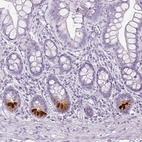

Immunohistochemistry analysis in human small intestine and skeletal muscle tissues using HPA048334 antibody. Corresponding REG3A RNA-seq data are presented for the same tissues.